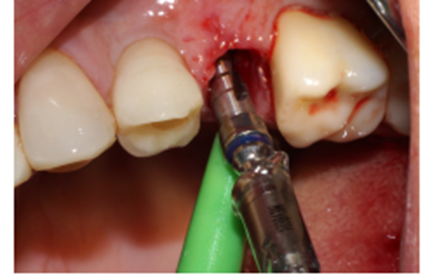

Foi eleito um implante Veloce Cone Morse de 3.75 X 11.5 mm e após a exodontia, o implante foi instalado utilizando o protocolo de fresagem recomendado pelo fabricante, fazendo uso das fresas escalonadas do sistema, alcançando um torque de inserção de 70 Ncm, o que me incentivou a promover o carregamento imediato deste implante (Figuras 5, 6, 7, 8, 9 e 10).